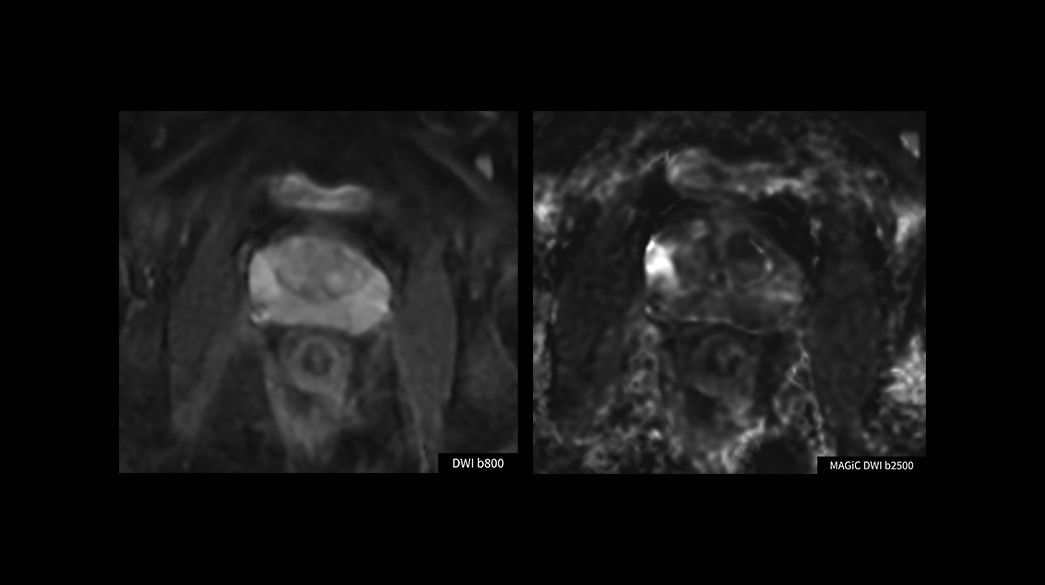

Fast

Advanced acceleration techniques for fast and reliable exams

Consistent

Motion and distortion-reduced scans with high-resolution and contrast